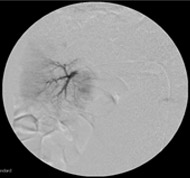

Nexsphere™, Nexsphere-F ™은 젤라틴 친수성 혈관내색전촉진용보철재로 치료 또는 처치목적으로 혈관색전술 진행 시 조영제와 함께 사용되는 의료기기로 혈관내로 카테터를 통해 주입되어 혈관을 일시적으로 폐색 시키는데 사용됩니다.

치료목적으로 동맥 또는 정맥 내의 혈류를 차단하기 위해 사용함